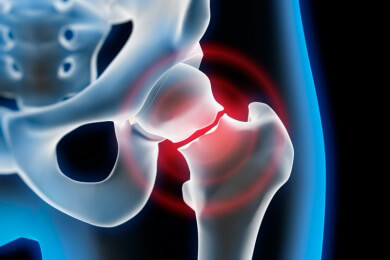

Am häufigsten sind die Unterschenkel und die Rippen von Knochenfrakturen betroffen. Auch Hüftfrakturen treten oftmals auf.

Oberschenkelhalsbruch - Ursachen, Symptome, Behandlung und Vorbeugemöglichkeiten